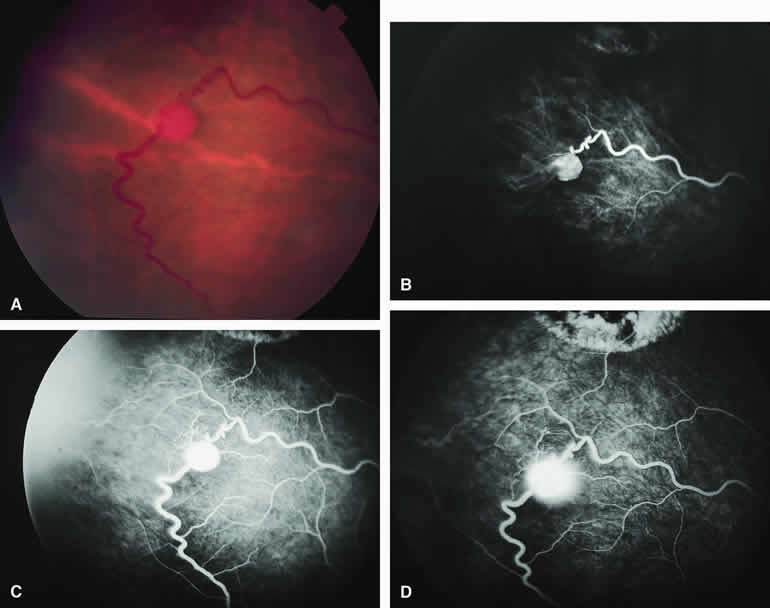

Choroidal Nevus Versus Melanoma with Overlying Serous Subretinal Fluid

A blister of serous subretinal fluid sometimes develops over and around a presumed choroidal nevus (Fig. 7A), especially if the lesion is located in the macula.11 If one performs a fluorescein angiogram on a small melanocytic choroidal lesion (nevus versus melanoma) that has shallow overlying serous subretinal fluid (see Fig. 7B, C, and D), one or more hyperfluorescent leak sites may show up slowly at the RPE level as the study progresses. In some cases, fluorescein will clearly leak from those foci into the overlying serous subretinal fluid. ICG angiography does not show hyperfluorescent leak sites at the RPE level as well as fluorescein angiography does.